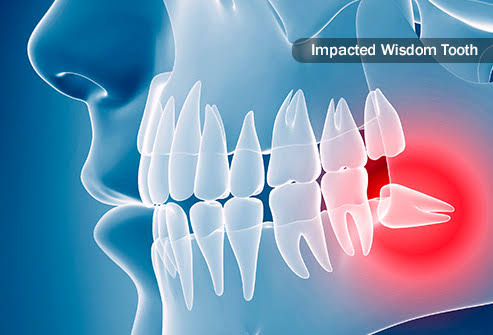

Oral and Maxillofacial Surgery

Dental surgery prices range from $320 USD to $380 USD. Prices vary because the Maxillofacial Surgeon might need to place bone or membrane to recover the area (not common)